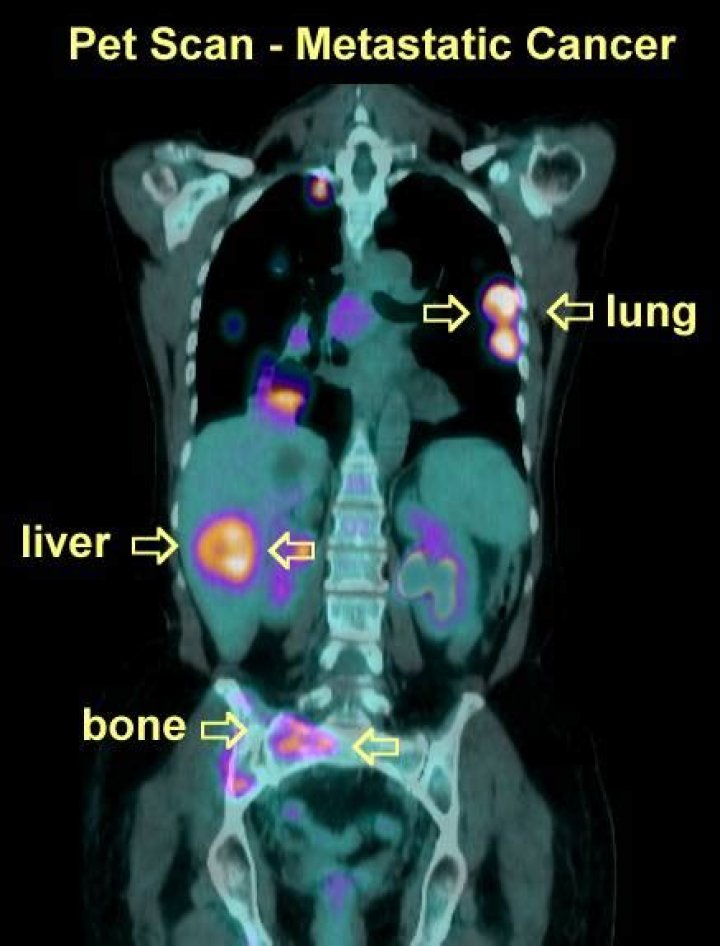

What color is cancer on a PET scan?

Cancer cells show up as bright spots on PET scans because they have a higher metabolic rate than do normal cells.

What does PET scan cancer look like?

The bright spot in the chest, seen best on the PET and PET-CT scans is lung cancer. Cancer cells show up as bright spots on PET scans because they have a higher metabolic rate than do normal cells.

PET scans can be used to determine how much cancer is in a person's body and how far the cancer has spread, which is called staging. Since PET scans can detect more cancerous sites than CT scans alone, they are often used in the initial staging and follow-up testing to see if and how the cancer is spreading.